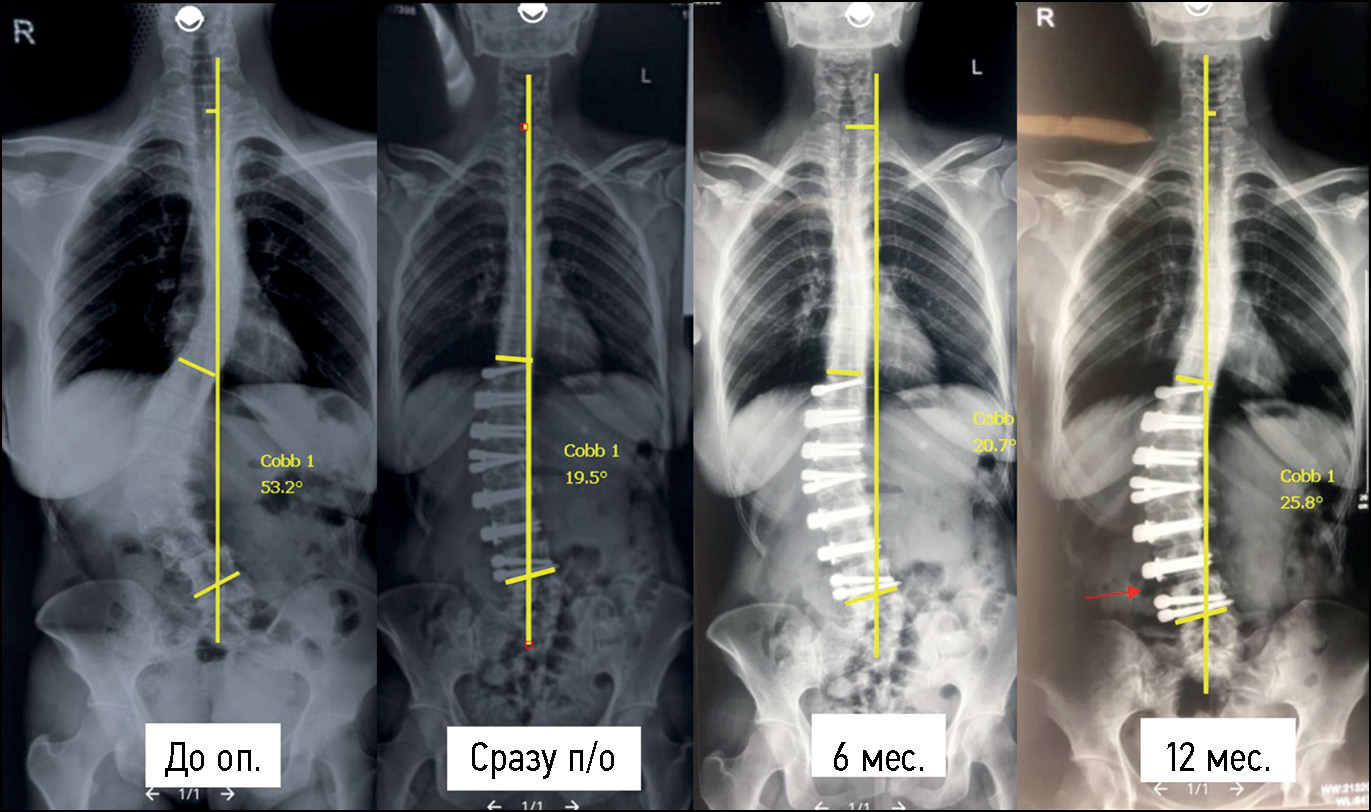

Two cases of cord rupture occurred after lumbar spine correction at the most distal level where no nucleotomy was performed. However, no significant loss of correction was observed after the repeat surgery (Fig. 4).

Fig. 4. AP X-ray of a 32-year-old female patient after lumbar spine anterior dynamic scoliosis correction at the observation stages. There is an increase in the angle between the heads of the L3-L4 screws (level where the nucleotomy was not performed) 12 months after the surgery. There is no significant loss of correction, dynamic monitoring is recommended.